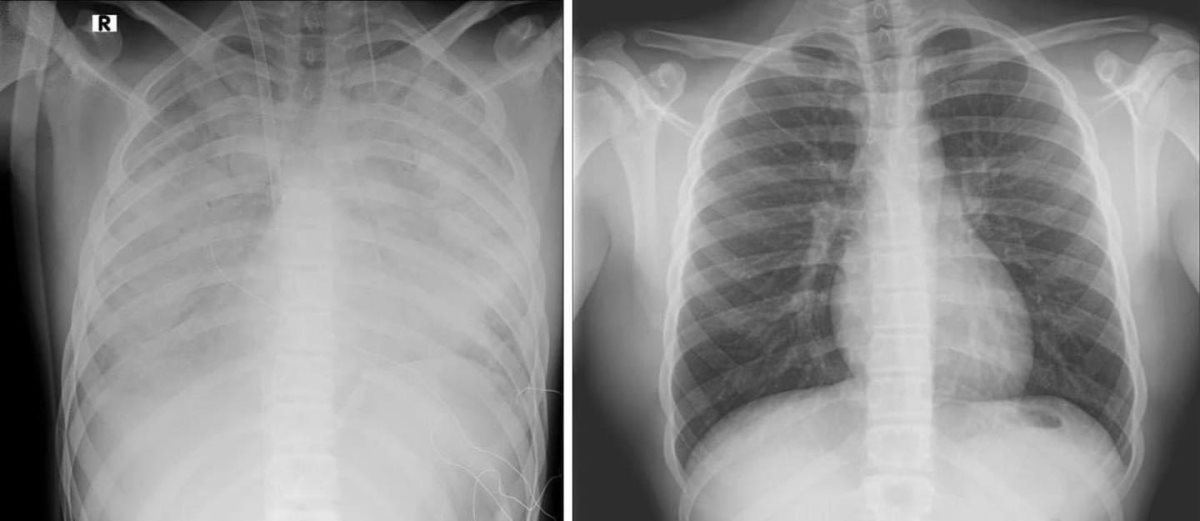

בתמונה: מימין צילום ריאות תקין, משמאל ריאותיו של הנערנער בן 16 אושפז במרכז שניידר במצב קשה עם קריסה של הריאות לאחר שימוש בסיגריות אלקטרוניות. הנער הובהל ליחידה לטיפול נמרץ לב, שם הוא מאושפז בהכרה ומחובר למערכת האקמו, המחליפה את פעילות הלב והריאות - כך מפרסמים הבוקר כתבי אתר ויינט, רענן בן צור וגד ליאור.